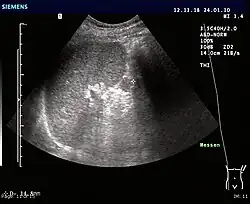

Accessory spleens may undergo hypertrophy after splenectomy[15] Very rarely, it may cause bleeding (pictured).[16]